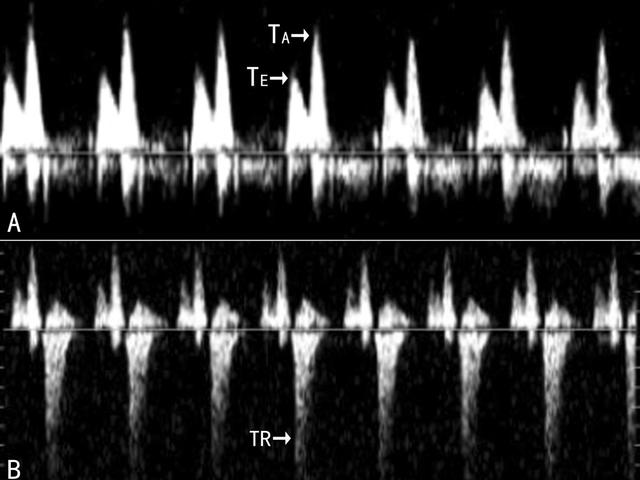

图4胎儿三尖瓣返流 A:正常三尖瓣血流 , B:三尖瓣返流血流(TR)